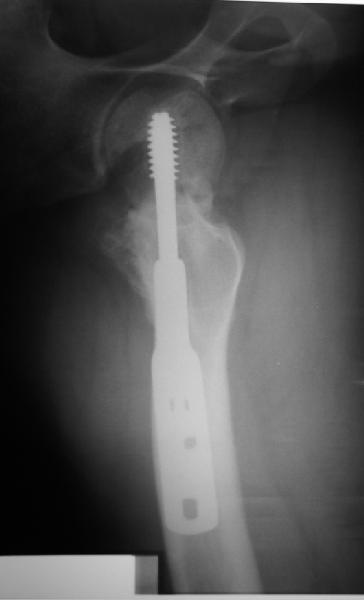

Пациент 20 лет  по поводу перелома шейки бедра оперирован в соседнем регионе 9 мес. назад.

На сегодня такая картина. Ходит с тростью, боли практически нет. Направили для эндопротезирования. У нас намерения больше в сторону вальгизируюещей остеотомии. То ли потом фиксировать как есть, то ли на уровне несращения шейки что-то подправить. Какие будут предложения?